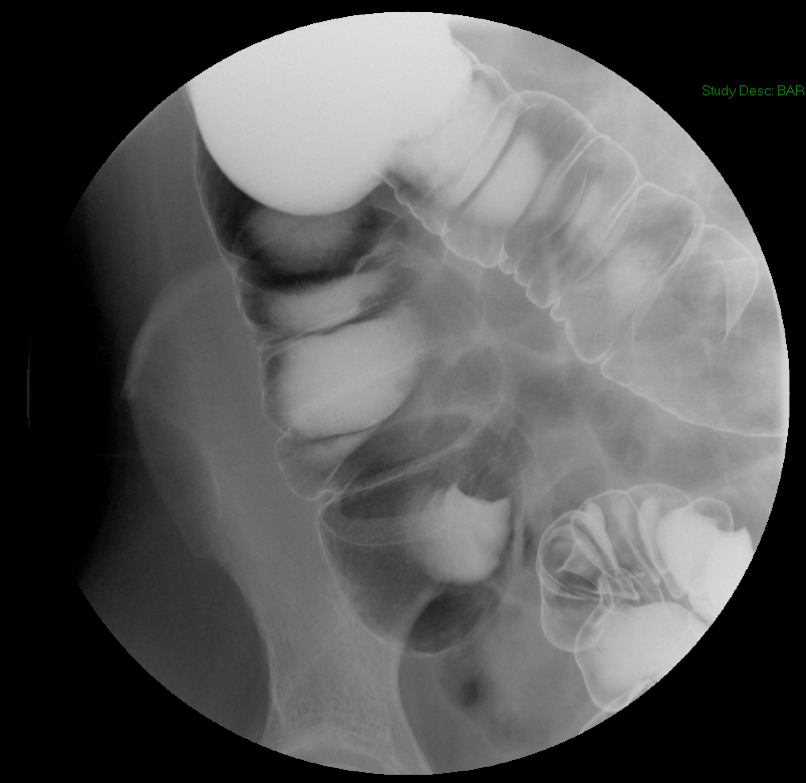

- With the patient seated on the defecography chair, obtain a scout image of the rectum and pelvis.

(key image 1). Be sure to include:

- the sacrum posteriorly

- the pubic symphysis anteriorly

- approximately 5cm below the skin surface of the perineum

- This extra room inferiorly will able you to view any prolapse that may occur without having to move the fluoro machine.

- the centimeter marker on the commode

- the barium-filled small bowel superiorly

- After obtaining the scout image, lock the fluoro tower in place.

- Do not move the tower after you have taken the scout image.

- This will ensure that you are able to measure descent of the pelvic floor appropriately.